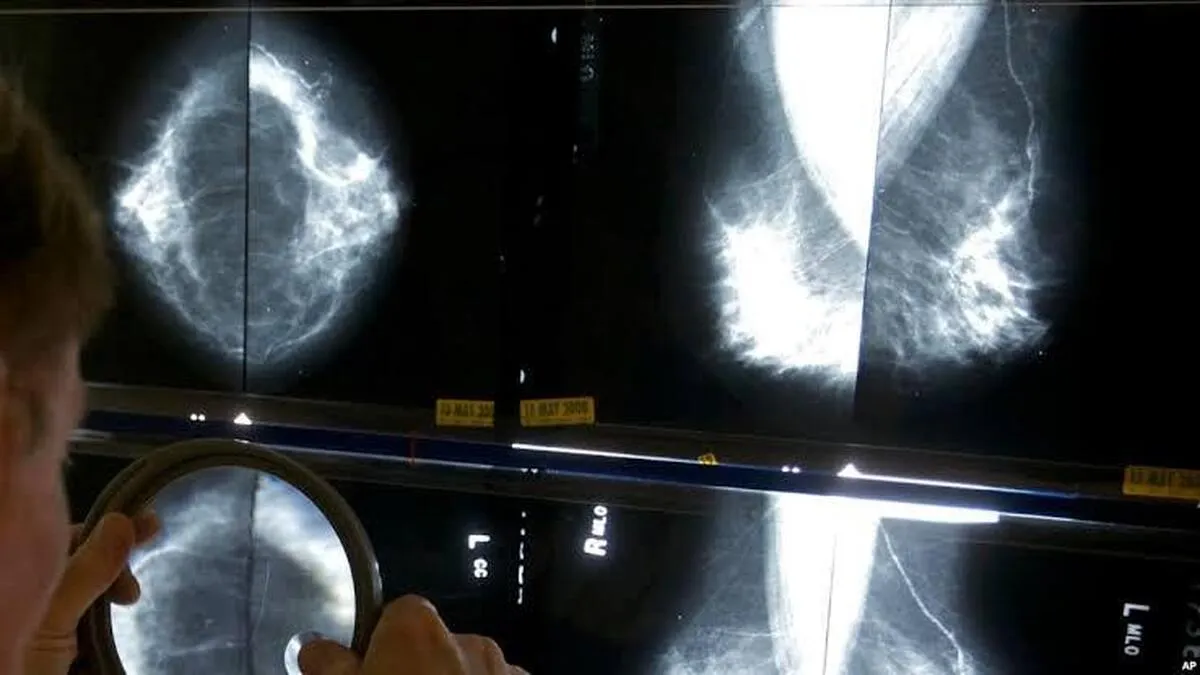

في خطوة علمية نوعية، طور باحثون إيرانيون نظاماً ذكياً يعتمد على الذكاء الاصطناعي لتحليل صور الماموغرافيا والمساعدة في الكشف المبكر عن سرطان الثدي.

أفادت وکالة آنا الإخباریة، وصرح الدكتور مهران عرب أحمدي، أخصائي الأشعة ومدير قسم البحث والتطوير في الشركة، إن المشروع يهدف إلى الكشف المبكر وتقليل حالات إغفال الآفات السرطانية في صور الماموغرافيا لدى المريضات.

وشدد عرب أحمدي علی أن إجراء فحوص الماموغرافيا للنساء فوق سن الأربعين يمثل الوسيلة الأساسية للكشف المبكر، مشدداً على أن اكتشاف الأورام الصغيرة في مراحلها الأولى يساهم بفعالية في تحسين نتائج العلاج وخفض معدلات الوفيات.

وأعلن مدير البحث والتطوير أن الشركة قامت بتصميم وتطوير نظام مساعد للأشعة قائم على الذكاء الاصطناعي لتشخيص الكتل والنتائج المشبوهة في سرطان الثدي، لافتاً إلى أن فكرة المشروع بدأت عام 2019، وأن النظام يُستخدم حالياً في نحو 30 مركز تصوير طبي في مختلف أنحاء البلاد.

وبيّن أن دمج هذا النظام مع عمل أخصائيي الأشعة أدى إلى رفع حساسية التشخيص بنسبة 20 بالمئة، وتقليل الإحالات غير الضرورية للتصوير الإضافي بنسبة 10 بالمئة، نتيجة زيادة الثقة لدى الأطباء أثناء تحليل الصور.